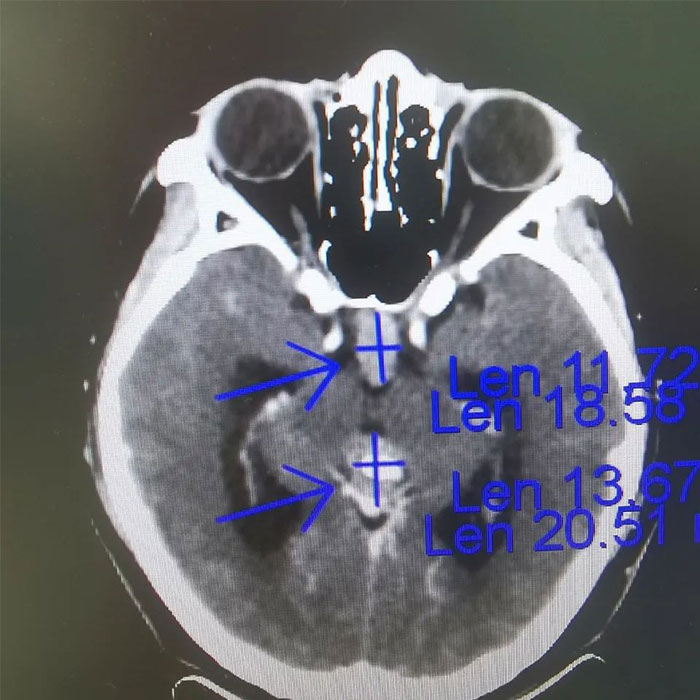

▲ 放療前病灶影像定位

腫瘤科(放療)王曉東主任詳細瞭解了患者的病史,並進一步完善檢查。在查體時,小剛表示近期感到頭痛,偶有噁心嘔吐。垂體增強MRI示:垂體術後,垂體區及松果體區佔位,視交叉受壓,右側海綿竇局部受累,第三腦室擴大,梗阻性腦積水形成,提示病情進一步加重。